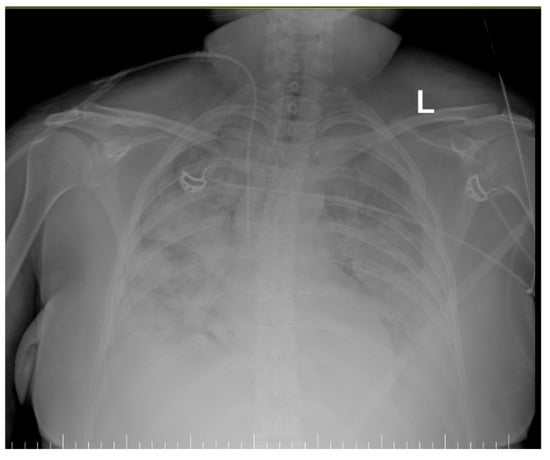

- Inhomogeneous veiling of the entire left lung field and, respectively, ½ of the right lung field—foci of pulmonary condensation and atelectasis. Bilateral pleural effusion. ECMO cannula at the level of the right internal jugular vein.